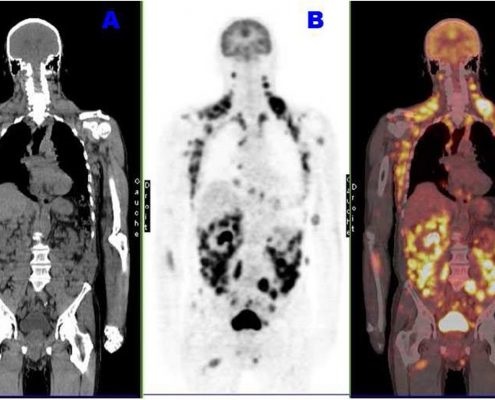

Une liquide contenant des molécules de sucre

marquées ( fluorodeoxyglucose ) par une très faible

dose de radioactivité est injecté dans les

veines avant de passer au scanner (B). Ce sucre

radioisotope marqué va se concentrer dans les zones

très actives : le cerveau, le cœur… mais également

dans les zones présentant une infection, une tumeur,

ou une maladie inflammatoire. |

L’image obtenue

par la TEP est fusionnée par l’image scintilographie

obtenue (B) et image TDM coronal (A) |